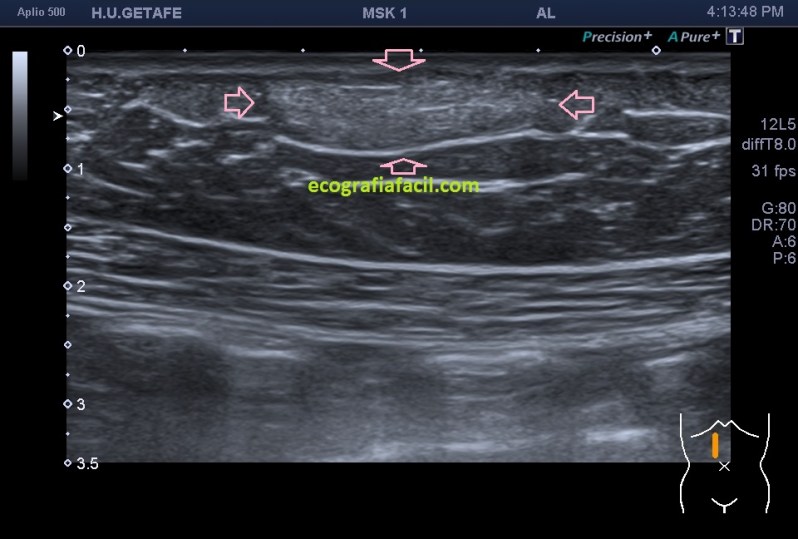

Normalmente encontraremos una lesión bien definida, hiperecogénica o isoecogénica con los márgenes definidos, en ocasiones lobulados, pero casi siempre ovalados con su eje largo paralelo a la piel en el plano subcutáneo y sin vascularización. Así, mira:

La estructura que estamos estudiando en este Caso 1, en las imágenes 1 a 6, es el estudio de protocolo de cualquier lesión, localización (flechas rosas), medición, vascularización. La 7 te marca una situación habitual en el estudio de los lipomas, y es que la paciente se nota un bulto, pero en la misma exploración descubrimos más, como es la pequeña lesión hiperecogénica que está justo al lado de la lesión mayor y palpable. Algunos de ellos, repito, pueden ser imperceptibles para la paciente, como era este caso. La imagen 8 es otra lesión próxima que sí era palpable.

En este caso las lesiones son todas hiperecogénicas comparativamente con el tejido hipoecogénico de la grasa del tejido celular subcutáneo. Son más o menos ovaladas, su eje largo es paralelo a la piel, no tienen vascularización y tienen medidas distintas. El diagnóstico final fue de lipomas. La paciente tenía más en la extremidades.

Cuidado, estas lesiones pueden presentarse hipoecogénicas, en ocasiones es complicado encontrarlos y es el reborde el que nos marca la posición de la lesión.